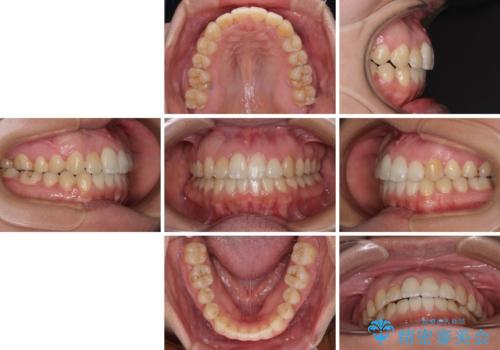

- 上下のデコボコを改善したいとのことで来院された患者様です。

近々妊娠する予定であり、極力短期間で治療したいとのことで、ワイヤー装置による非抜歯矯正治療を行うこととしました。

治療開始後すぐに妊娠され、つわりと闘いながらの矯正治療となりました。

上下顎でゴムかけを行ったのですが、早く終わらすためにしっかりと装着していただき、無事出産前に装置を外すことができました。